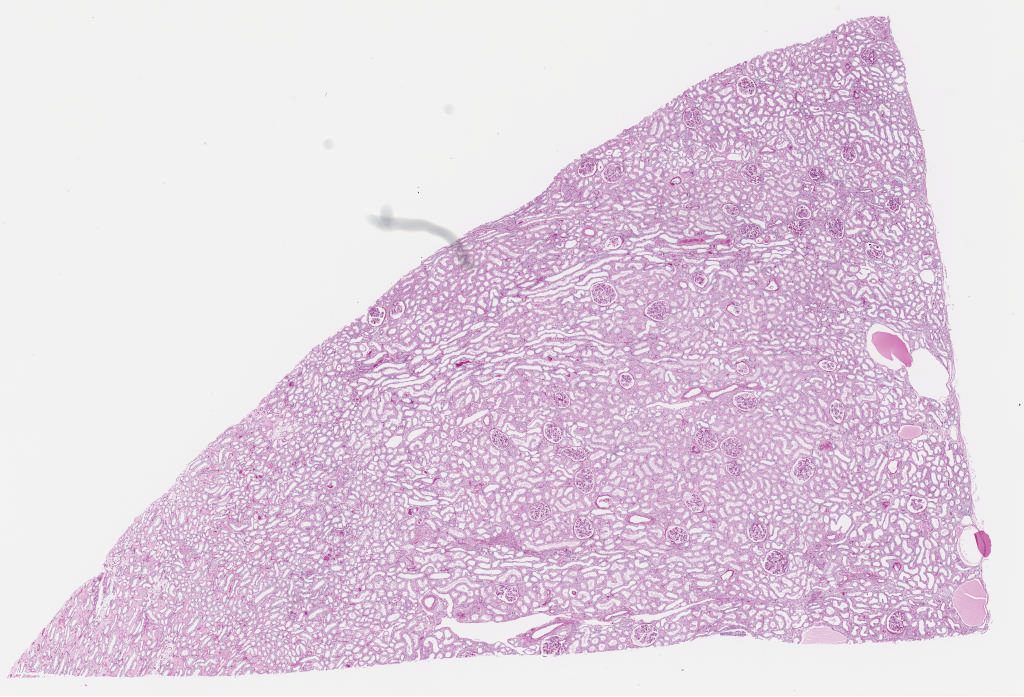

Q - PAS Kidney.svs

32367 x 22013

@ 40X